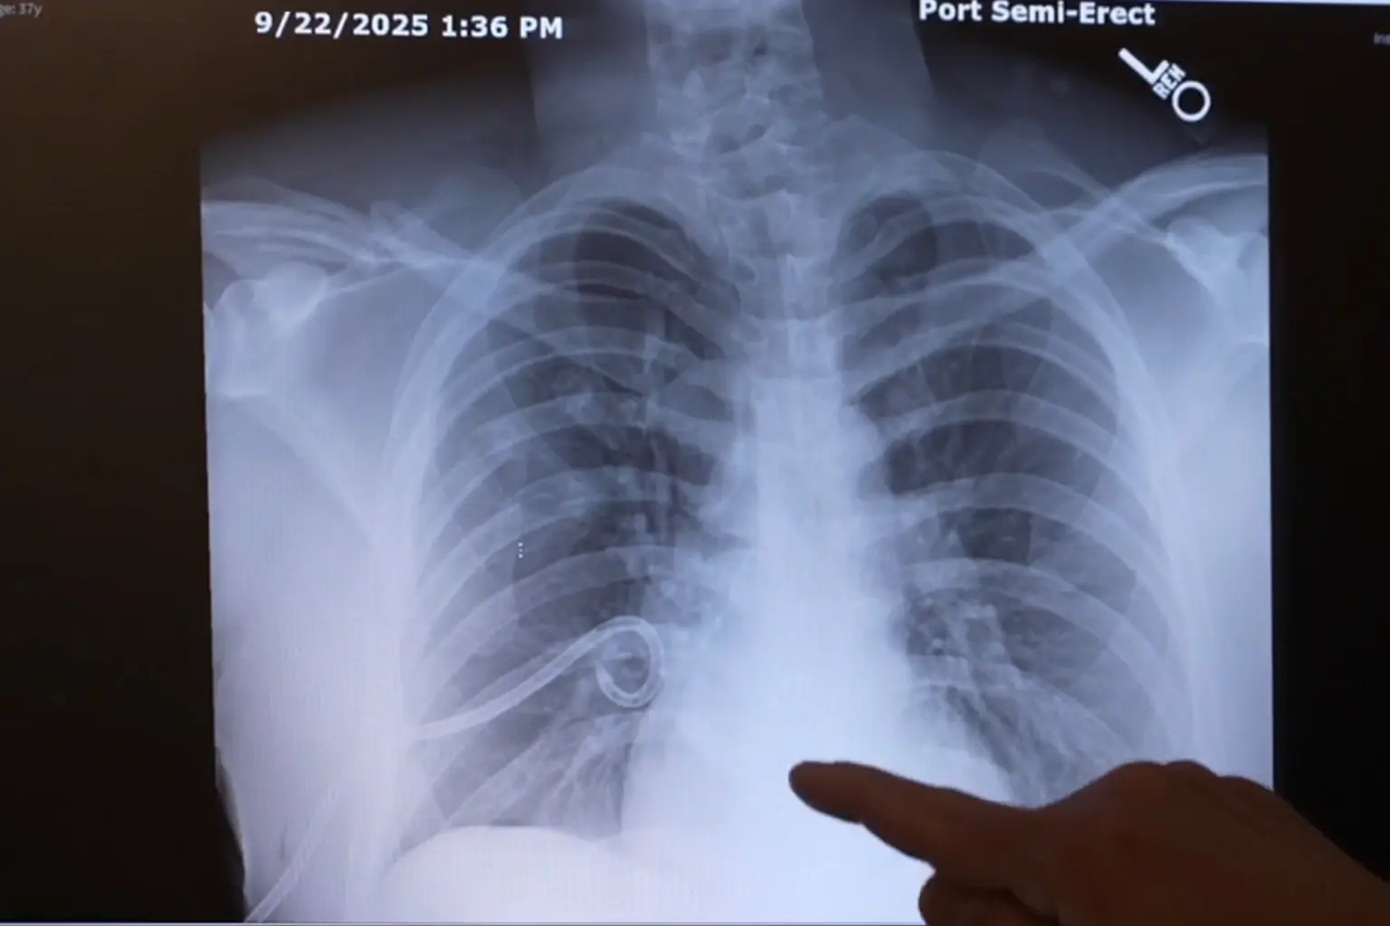

Ο Μπεμ βρέθηκε να κατρακυλά περίπου 15 μέτρα (50 πόδια) στο έδαφος, σπάζοντας την κλείδα του και επτά από τα 24 πλευρά του, ενώ υπέστη και πνευμονική κάκωση. Επίσης τραυματίστηκε σοβαρά στην πλάτη με μεγάλη τομή που προκάλεσε ο βράχος, αφού πρώτα τον είχε χτυπήσει στο κεφάλι.

Οι γιατροί στην Κλινική Billings συμφώνησαν πως θα μπορούσε να είχε πάθει «σοβαρή κρανιοεγκεφαλική κάκωση» που «θα ήταν απειλητική για τη ζωή του», αν δεν υπήρχε το κράνος, όσο φθαρμένο κι αν ήταν.